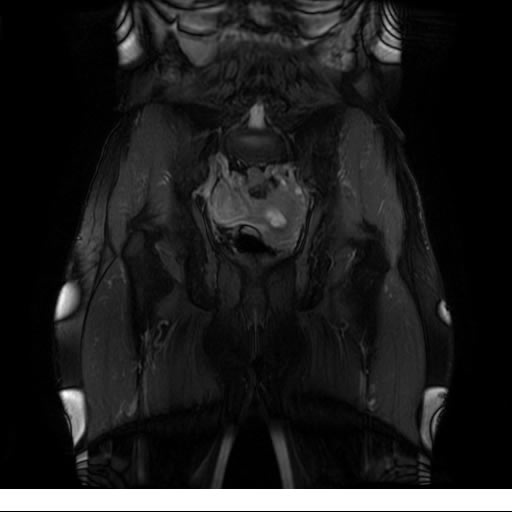

Se realizan adquisiciones en diferentes planos, con secuencias Spin echo y GRE, ponderadas a T1 y a T2, se utilizan pulsos de saturación de grasa y se administra medio de contraste a base de gadolinio.

El útero está en retroversión, retroflexión, y en posición central, se observa liquido en la cavidad endometrial, debido a la presencia de un Ca endometrial; en el anexo derecho se observa una masa quística que mide 3.8 x 2.2 cm de diámetro, corresponde a un quiste bilobulado, posee pared gruesa con componente solido puede tratarse de un Cistoadenocarcinoma, el cual realza con el medio de contraste de forma importante, entra dentro de una clasificación O-Rad tipo IV compatible con un Cistoadenocarcinoma

O-RAD tipo IV, Cistoadenocarcinoma